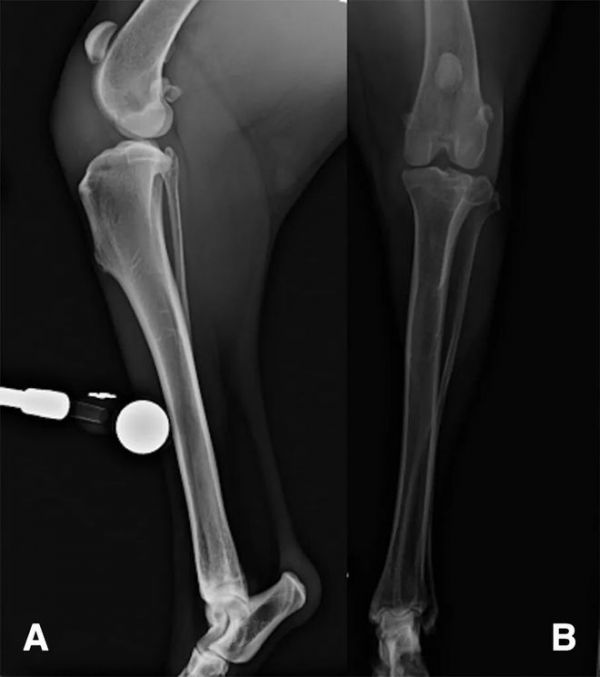

使用0.03mg/kg的乙酰丙嗪、0.01mg/kg的美托咪定和0.1mg/kg的美沙酮组合进行深度镇静,以进行膝部X线造影(图1)和超声检查(图2)。镇静检查期间唯一发现的异常是右侧髌骨韧带增厚。

图一 3岁白色瑞士牧羊母犬(已绝育),4周右侧盆腔肢体跛行病史,右侧膝关节侧位(A)和前后位(B) X线图。